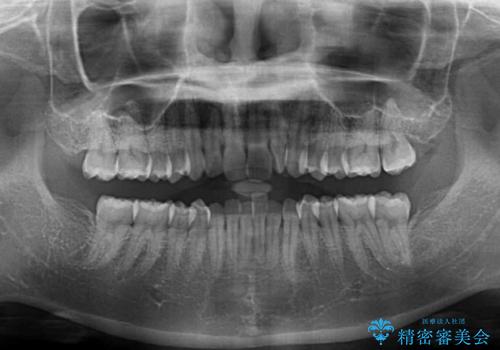

- 上下前歯のデコボコと深い咬み合わせを気にして来院された患者様です。

インビザラインによる上下歯列の拡大と、IPR(歯と歯の間を削る)にるスペースの獲得により、前歯のデコボコを改善することとしました。